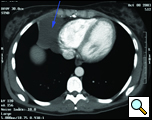

Patient is a 29 year old female, who was diagnosed with a pericardial cyst when she was 17 years old during a work-up of asthma. Recently, the patient presented with a persistent cough, and a repeat CT scan revealed increase in size of the cyst to approximately 6x6cm (Figures 1 and 2). Her past medical history was significant for Wolff-Parkinson-White syndrome. On examination no abnormalities were found. Since the cyst was enlarging, causing significant anxiety, and possibly contributing to her persistent cough, resection was recommended. Her cardiologists felt that her WPW Syndrome was not a contraindication to surgery.

| Figure 1. Preoperative Chest x-ray. | Figure 2. Chest CT scan showing right cardiophrenic pericardial cyst. |